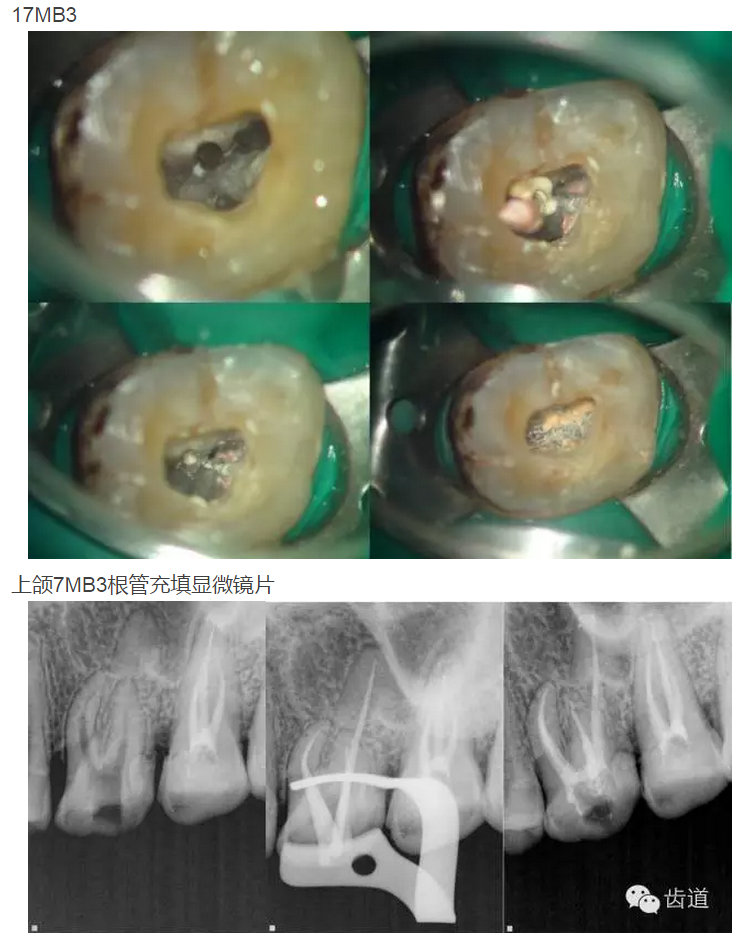

上頜第一磨牙:多為3-4個根管,MB2發(fā)生率約為60%;

上頜第二磨牙:與上頜第一磨牙相似,多為3根管,偶見雙鄂根管;